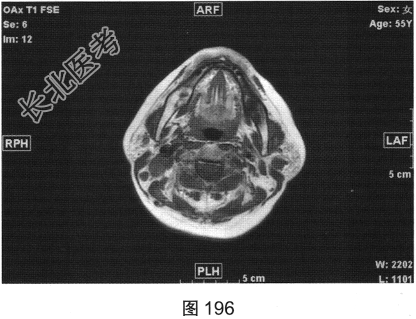

- 简答题2、患者行颈部平扫MRI检查,如图196~图199所示。请问患者MRI检查的阳性影像学表现有哪些?